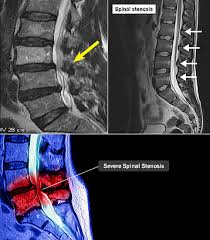

✅ 허리협착증이란?

허리협착증은 척추 속 신경이 지나가는 통로인 '척추관'이 좁아지면서, 신경을 눌러 통증이나 저림 등의 증상을 유발하는 질환입니다.

- 요추관협착증은 주로 허리 부분(L3~L5)의 협착으로 인해 발생합니다.

- 퇴행성 변화, 즉 디스크, 인대비후, 관절돌기 비대 등이 원인이 됩니다.